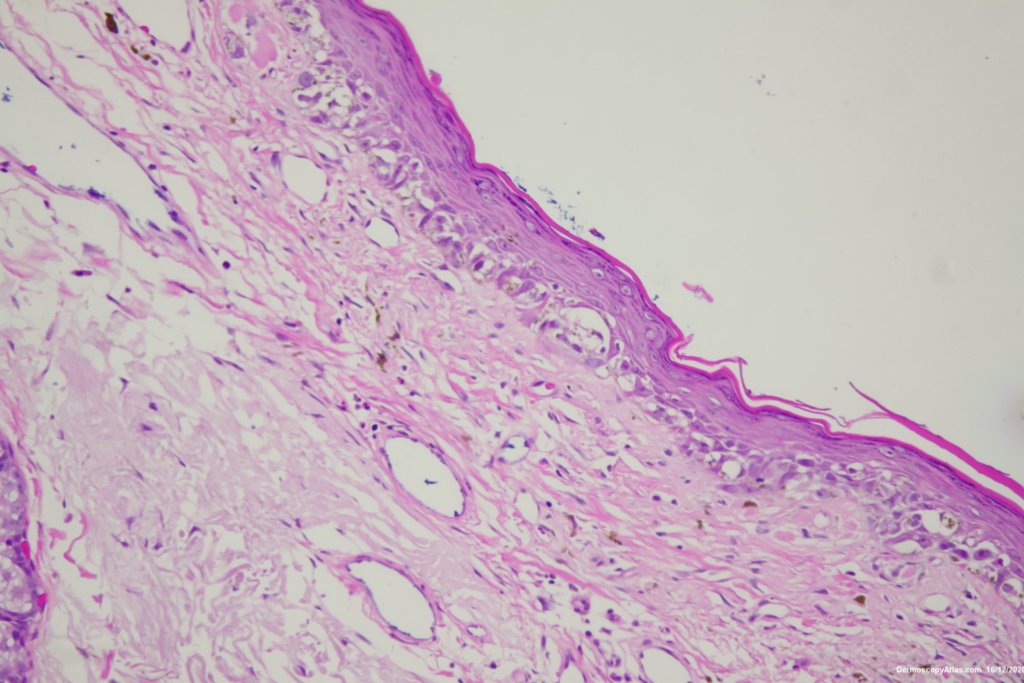

Image Number #3578 (Lentigo Maligna)

Diagnosis: Lentigo Maligna

Description: Pigmented lesion cheek and pink nodule

Elderly male with no past history of melanoma developed these two lesions over a year or so. The lentigo maligna was easy to diagnose on the clinical and dermatoscopy but the nodule was more difficult. Was it an amelanotic melanoma, BCC or SCC were the initial thoughts. Histology showed a well differentiated sebaceous carcinoma. The two lesions were excised in the same specimen with 5 mm margins. Studies failed to show the mutation for the Muir Torre syndrome which can be seen with sebaceous carcinoma.